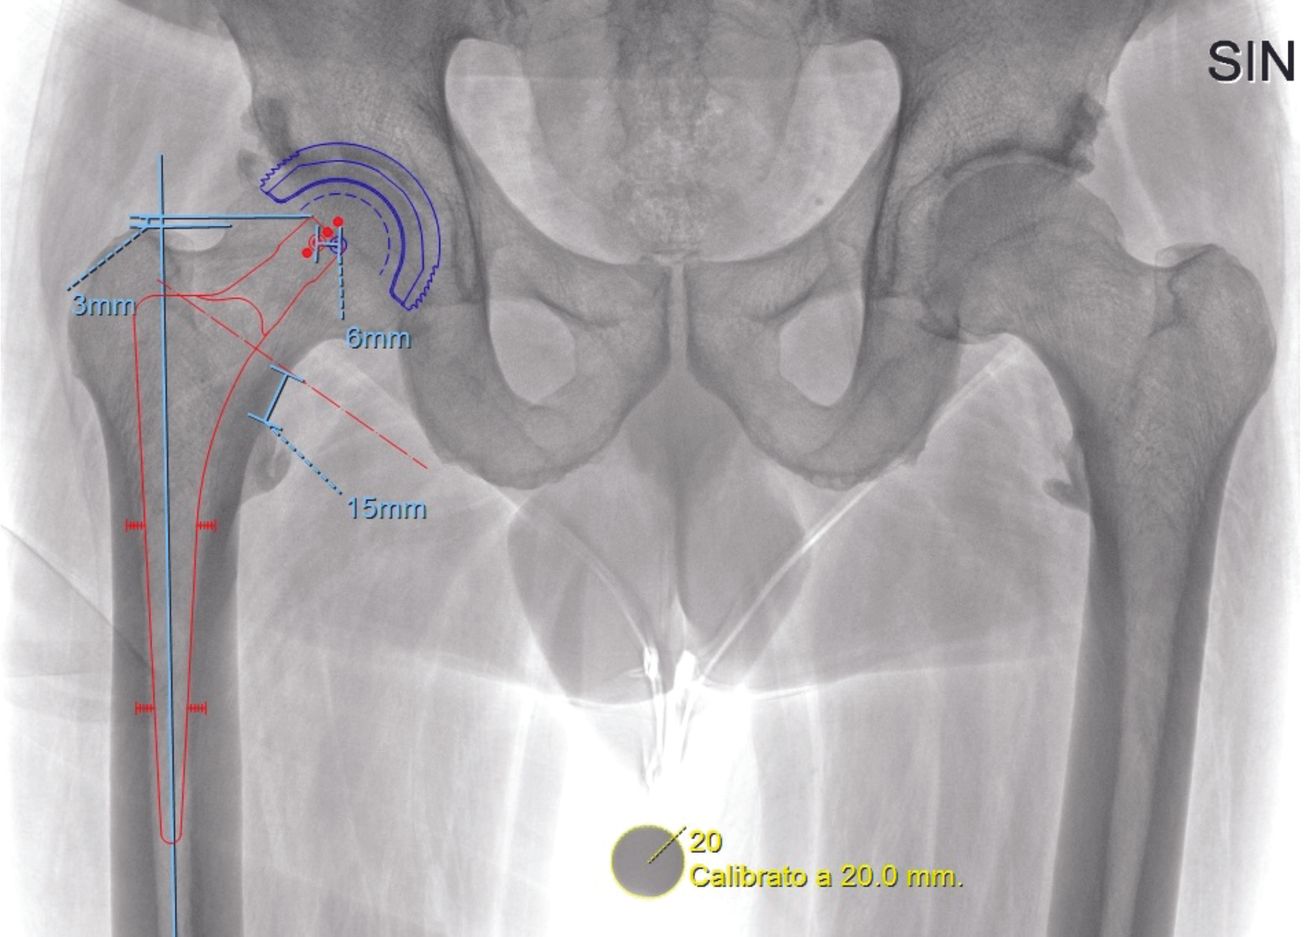

Médico-légal Comment une inégalité de longueur au décours d’une prothèse totale de hanche devient fautive ? , Nicolas Chanzy Chirurgien-orthopédiste conseil, MACSF, Paris, France 🖂 chanzy.nicolas@wanadoo.fr N°320 - Janvier 2023 ● 2 min de lecture